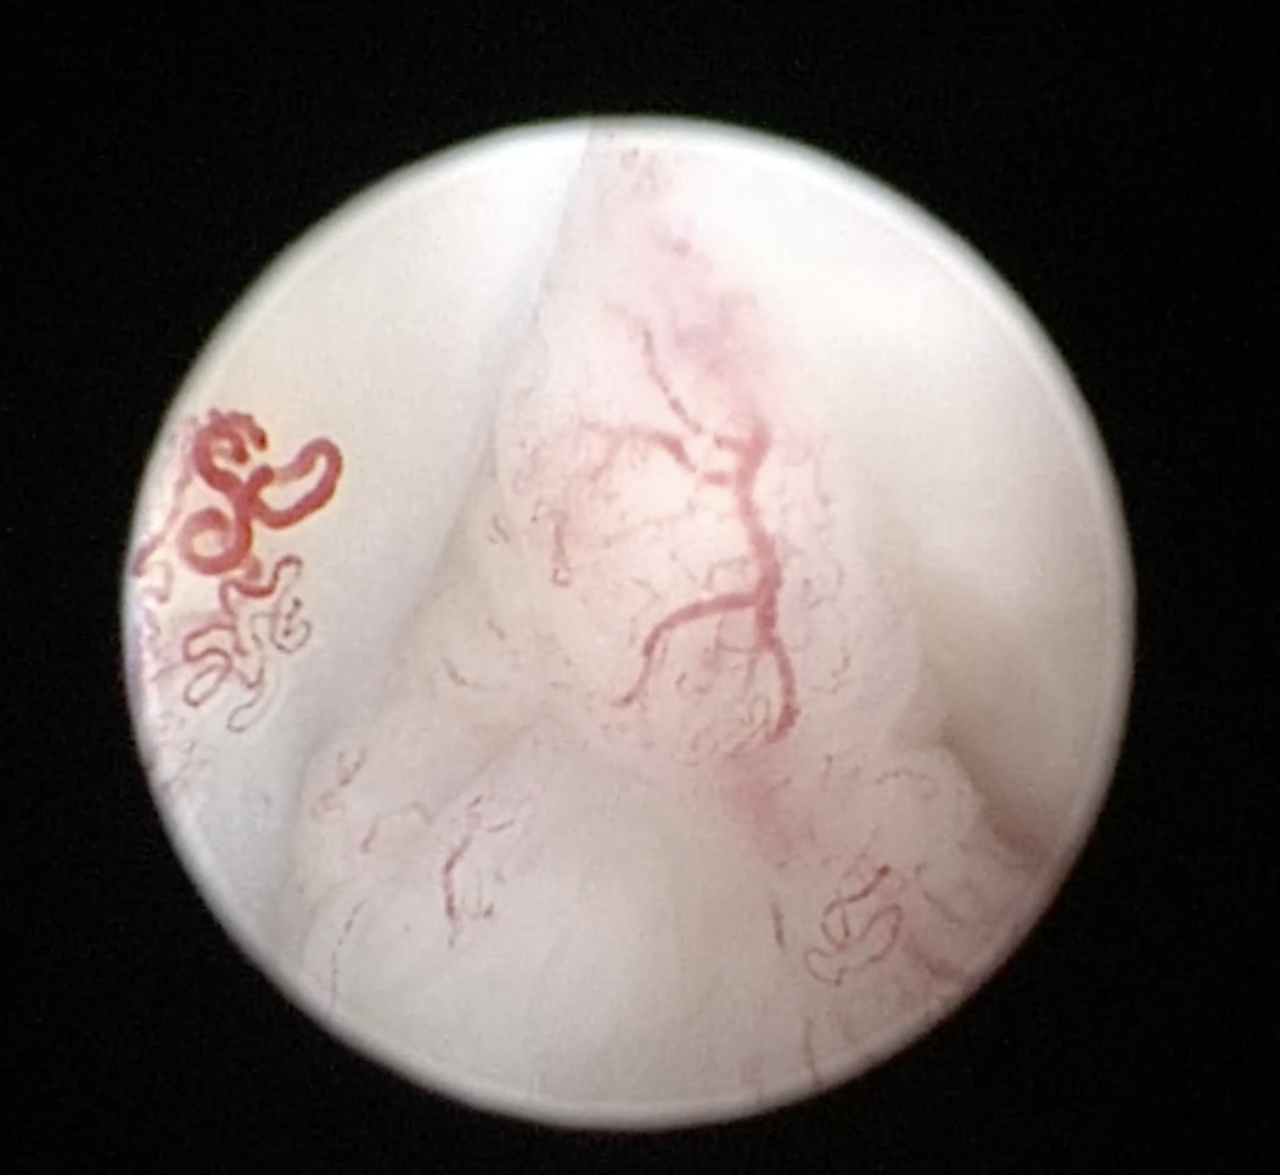

前十字靭帯(部分)断裂による跛行を示すワンコにCORA Based Leveling Osteotomyで対応しました。これによりTPAが29°から10°に矯正されます。体重の荷重時における前十字靭帯にかかる前方スラストと転がり運動時の負荷が取れ、部分断裂から完全断裂へ移行すること。さらに半月板損傷を予防することができます。早期のエックス線診断が治療介入の決め手です。しばらくは安静が必要です。